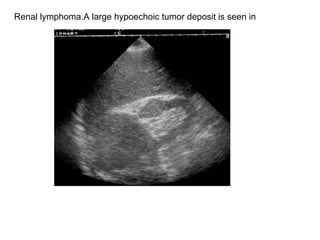

Renal lymphoma.A large hypoechoic tumor deposit is seen in